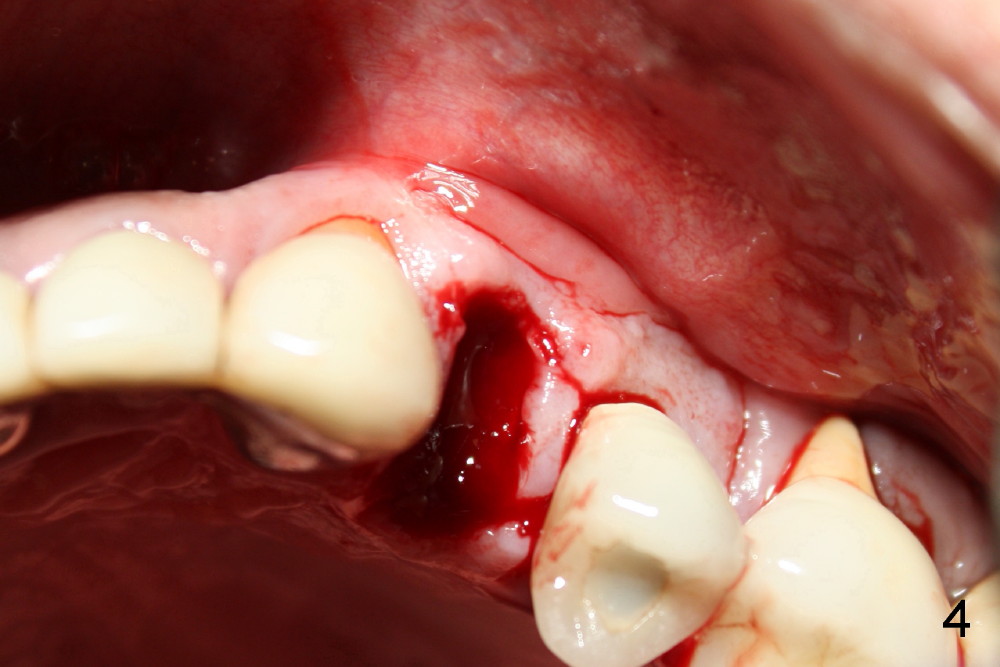

A 50-year-old man has mild pain in the upper left 1st bicuspid 3 years after root canal retreatment with placement of two posts (Fig.1). Findings of clinical exam are consistent with root fracture (Fig.2). Extraction reveals two fused roots (Fig.3,4). Probing indicates that the buccal plate is defective. Osteotomy is initiated in the palatal socket with a 2 mm pilot drill, followed by 2.5 and 3.0 mm reamers and 4.5x20 mm tap. The septum appears to have been pushed buccally (Fig.5 *) and form a new buccal wall (partially, strengthened by bone graft mentioned below) for the implant to be placed. The implant (4.5x20 mm) is placed in the palatal socket (Fig.6 *) with insertion of an abutment (A: 3.5x5 mm 0º), while a mixture of autogenous bone (harvested from reamers) and Synthograft (Bicon) is placed in the shrunken buccal socket (Fig.7; using allograft may decrease postop bony shrinkage). The bone graft is then contained by an immediate provisonal without collagen membrane or flaps. The patient is doing well postop. The gingiva is healthy (Fig.8*) when the provisional is removed 3 months postop with normal papillae (Fig.9 arrowheads). It remains the same 1 month post cementation (Fig.10,11). For further follow up, see immediate implant of the tooth #13.